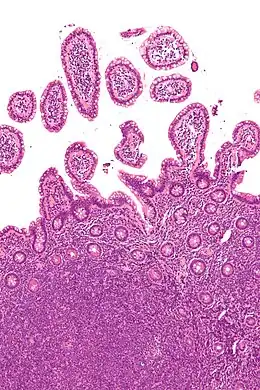

Les lymphomes non hodgkiniens sont des néoplasies développées à partir des tissus lymphoïdes, qui ne sont pas des lymphomes de Hodgkin.

Un lymphome est un cancer du système lymphatique aux dépens des lymphocytes. Le système lymphatique comprend la moelle osseuse, la rate, le thymus, les ganglions lymphatiques et les vaisseaux lymphatiques ; il assure la défense de l'organisme contre les microbes, parasites, toxines, corps étrangers, etc.